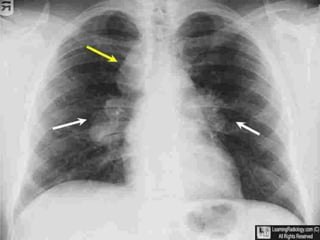

RADIOGRAPHIC FEATURES

• Chest radiograph abnormal in 90% of sarcoidosis

patients.

• Bilateral hilar lymphadenopathy in 50-85%cases.

• Lymph nodes big and sharply defined with clear line

of transluscency between mediastinum and lymph

nodes- POTATO NODES.

• Unilateral lymphadenopathy- rare

• Pulmonary infiltrates in 25-60% cases

Sarcoidosis stage I: left and right hilar

and paratracheal adenopathy

(1-2-3 sign)

STAGE I - Thoracic lymphadenopathy.

Normal lung parenchyma (50%)

ADENOPATHY AT TIME OF DIAGNOSIS

Marked enlarged hilar and mediastinal

lymph nodes

Radiographic abnormalities on chest x ray.